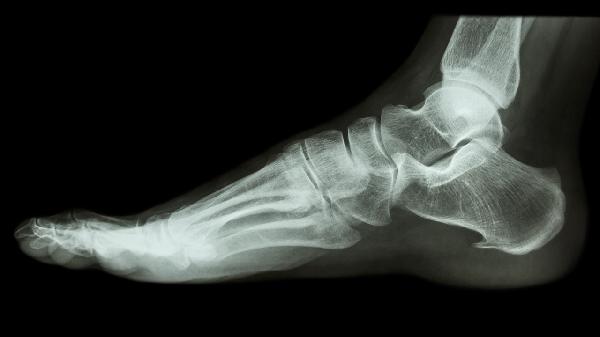

少数情况下脚趾骨折可能符合评级条件。开放性骨折伴严重软组织损伤、骨折畸形愈合导致足弓结构改变,或继发创伤性关节炎持续影响行走功能时,经劳动能力鉴定委员会确认后可评定伤残等级。但此类情况需提供完整医疗记录及影像学证据,证明功能障碍与骨折直接相关且持续存在。